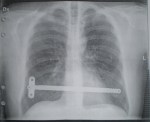

X-Ray:

I guess I can’t get through airport security checks anymore…